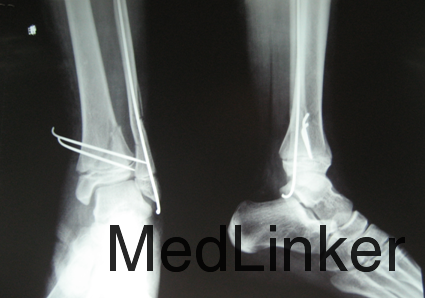

诊断:左胫骨远端骨折 治疗:消肿止疼治疗,择期行骨折闭合复位克氏针内固定术

术后给予患者抗炎之疼消肿冷疗等对症治疗,术后指导患者功能锻炼,术后每个月复查,术后三个月取出克氏针